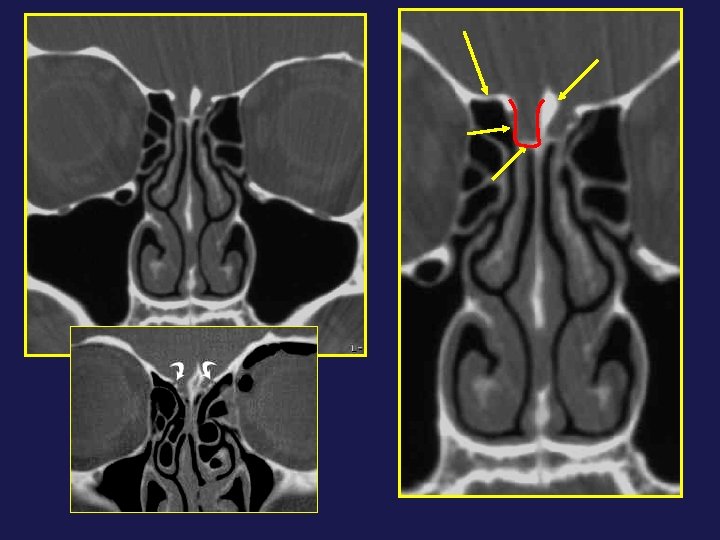

Ostium frontal + processus unciné : son insertion supérieure est un repère anatomique important

Ostium frontal + processus unciné : son insertion supérieure est un repère anatomique important TYPE 2 TYPE 3 TYPE A TYPE 1 A B C Friedman et coll, 2004

Récessus frontal + cellules de l’Agger Nasi : Pneumatisation des cellules de l’AN →

Récessus frontal + cellules de l’Agger Nasi : Pneumatisation des cellules de l’AN → calibre du RF Récessus étroit = canal frontonasal